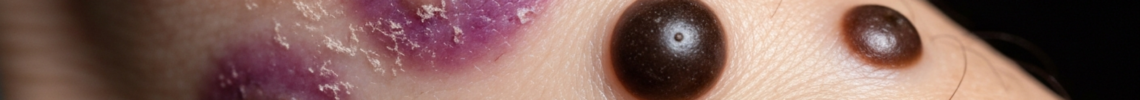

• Plaques: Progression from patches leads to plaques, which are elevated, flat-topped lesions. Kaposi’s sarcoma plaques are typically firm to the touch and can be a few millimeters to several centimeters thick. Their color remains within the spectrum of red, purple, or brown, often with a more intense violaceous (violet-blue) tint. These Kaposi’s sarcoma images often highlight the distinct elevation and firmness.

• Nodules: Further progression results in the development of nodules, which are distinct, raised, solid lesions that are usually rounded or dome-shaped. Kaposi’s sarcoma nodules are often firm and rubbery. They can vary considerably in size, from small, pea-sized lesions to larger, golf ball-sized masses. These Kaposi’s sarcoma pictures clearly show the three-dimensional aspect of the lesions.

• Coloration: The hallmark color is violaceous, ranging from reddish-purple to dark brown or black. This distinct coloration is a key diagnostic clue in Kaposi’s sarcoma images. The color can change over time within the same lesion, often becoming darker as the lesion matures or if it undergoes hemorrhage.

• Pigmentation: The color spectrum is critical – from faint pinkish-red to deep violaceous purple or dark brown/black. The darker hues often indicate older, more mature lesions or those with internal hemorrhage.